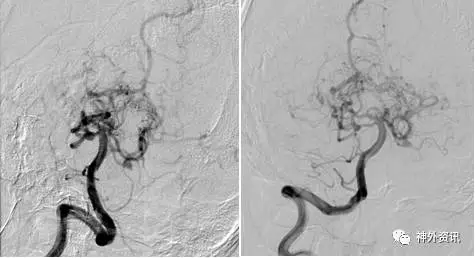

(DSA:烟雾病;左侧大脑后动脉P2段夹层动脉瘤)

(3D重建:动脉瘤形态极不规则,远/近端血管迂曲严重伴狭窄)

(左:Envoy DA导引导管-右侧椎动脉V3段;右:支架导管成功超选左侧大脑后动脉)

(支架辅助弹簧圈栓塞-动脉瘤不显影,载瘤动脉通畅)

(术后3D双容积重建)